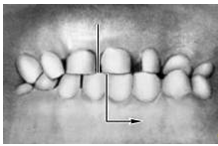

Кроме аномалий П. в сагиттальной плоскости существуют аномалии П. в вертикальной и трансверзальной плоскостях. К основным вертикальным аномалиям (определяются по отношению к горизонтальной плоскости) относится открытый и глубокий П. Открытый П. (рис. 7, а) — наличие щели между зубными рядами при их смыкании, чаще в области передних зубов, реже в области боковых. Иногда смыкаются только последние моляры, что приводит к выраженным нарушениям жевательной функции и особенно речи. При глубоком П. (рис. 7, б) передние зубы одной из челюстей в значительной степени перекрывают коронки зубов-антагонистов, нижние резцы не опираются на зубные бугорки верхних резцов, а соскальзывают к их десневому краю, что приводит к постоянному травмированию десен и неба; нижняя часть лица укорочена за счет уменьшения или дистального положения подбородка.

Рис. 7а). Схематическое изображение челюстей при открытом прикусе.

Рис. 7б). Схематическое изображение челюстей при глубоком прикусе.

Рис. 7в). Схематическое изображение челюстей при перекрестном прикусе.